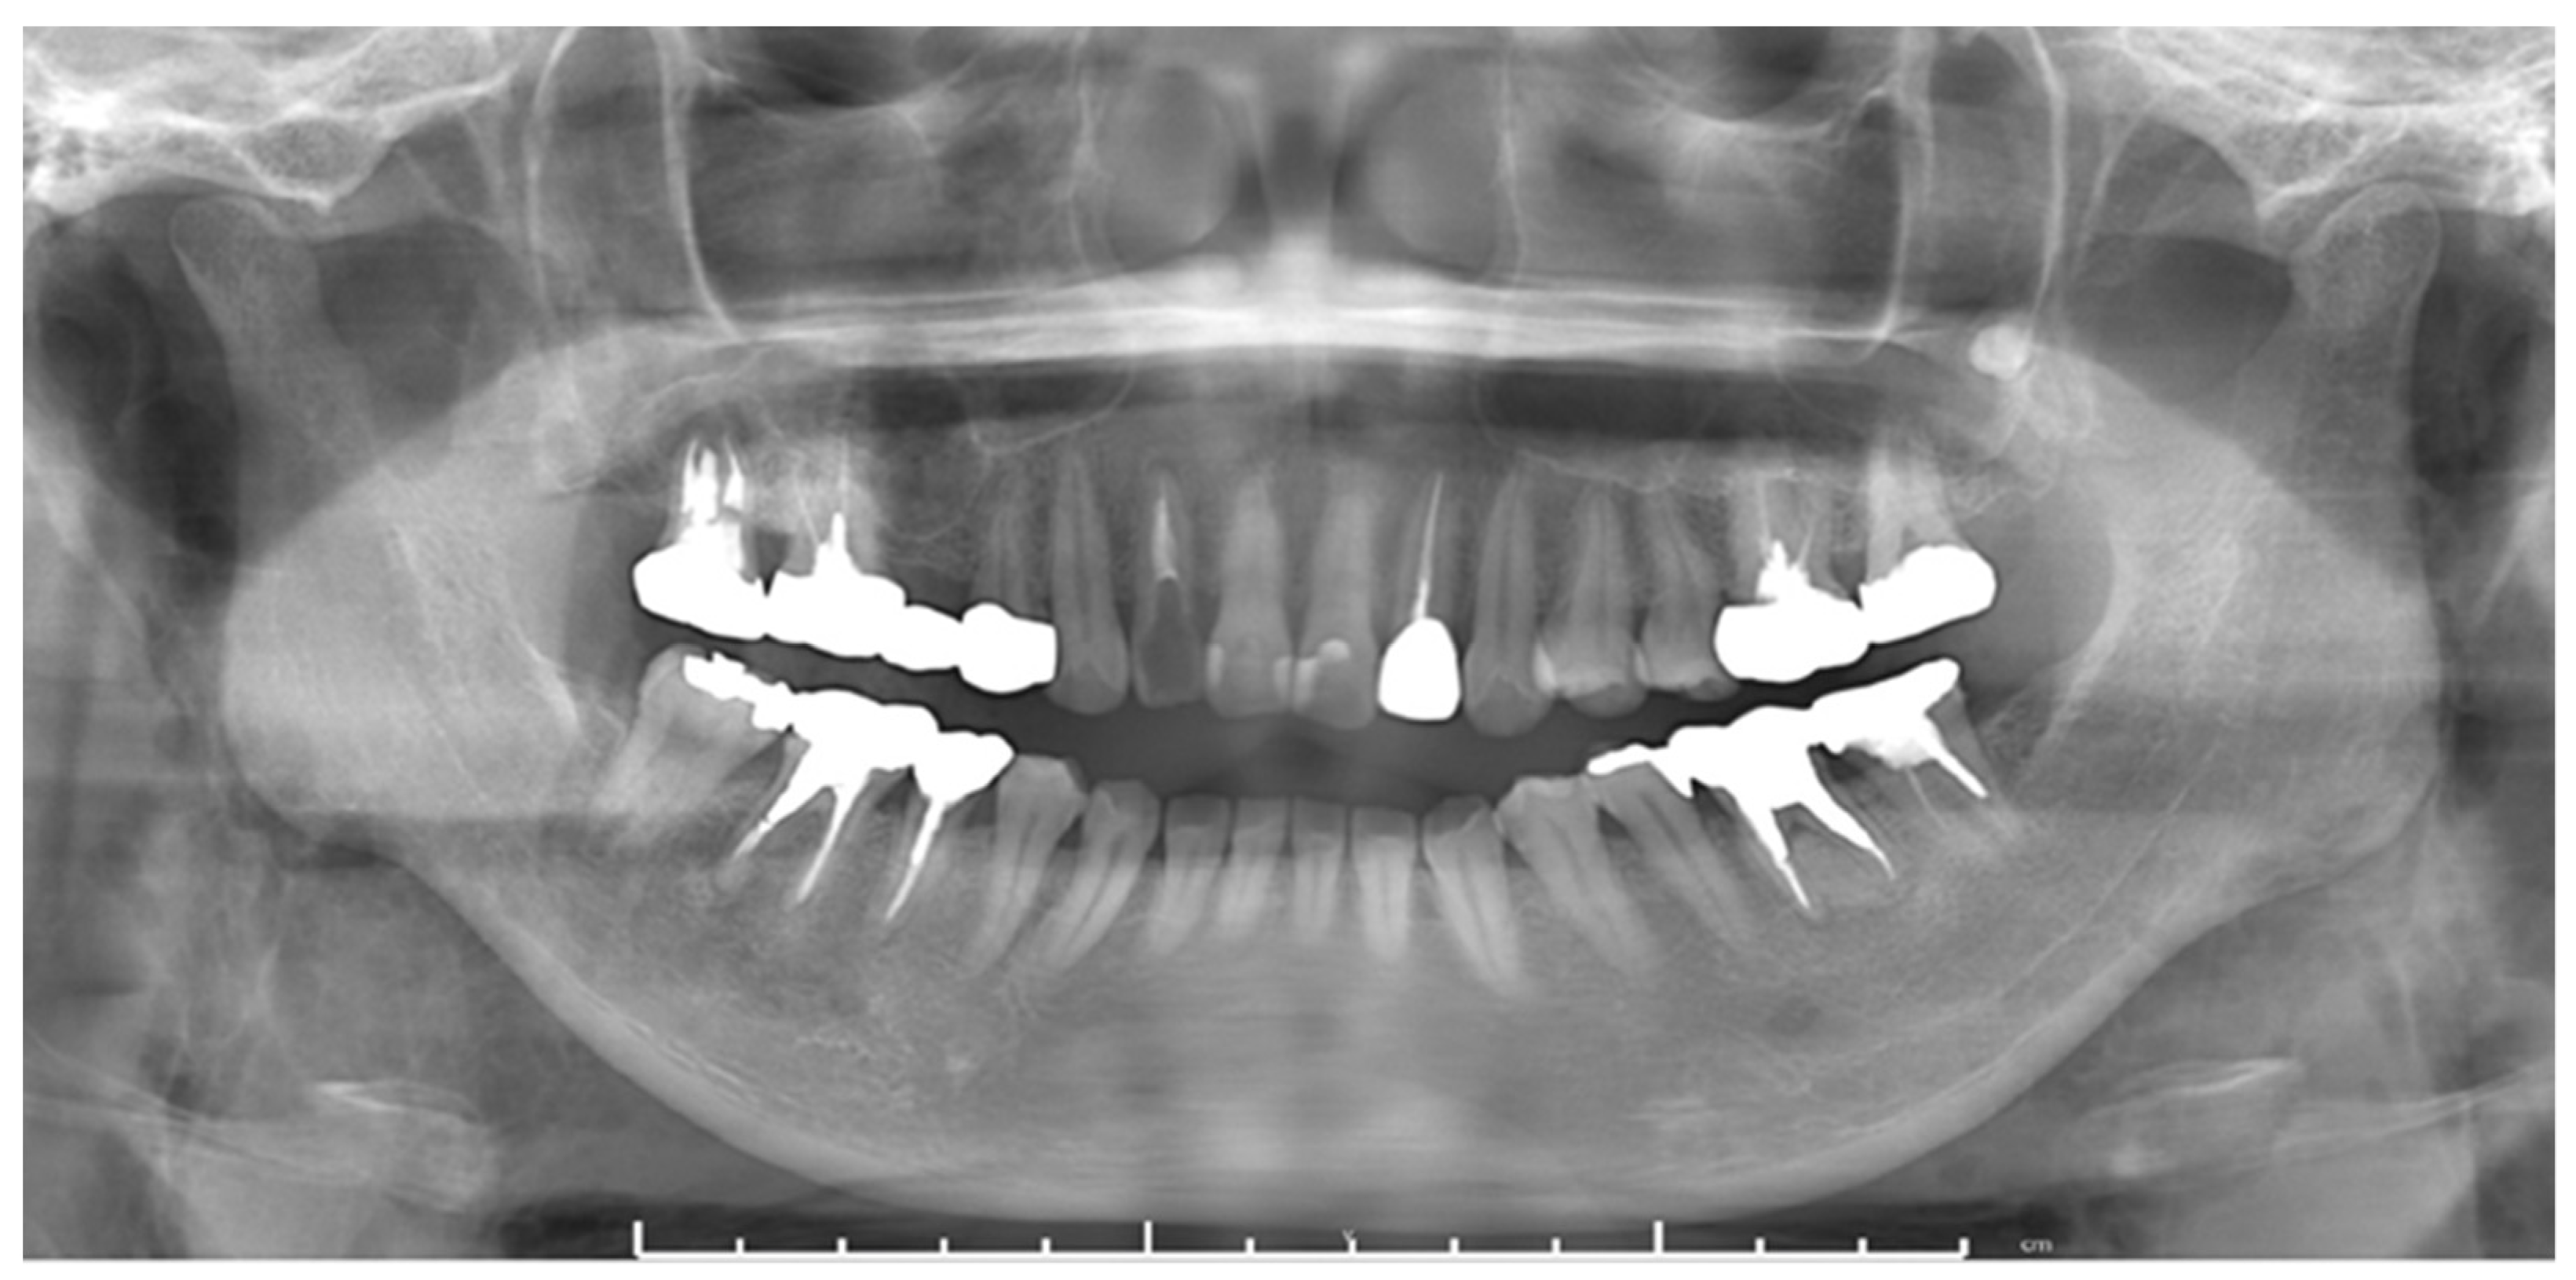

2.3.1. Case 1

2.3.2. Case 2

2.3.3. Case 3